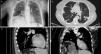

Mujer de 76 años, no fumadora, intervenida de quistes hidatídicos hepáticos 8 años antes. Consultó por cuadro de 4 días de evolución caracterizado por tos, expectoración purulenta sin fiebre y disnea. En la exploración destacó una hepatomegalia no dolorosa. La radiografía de tórax (fig. 1A) reveló múltiples nódulos de diversos tamaños en ambos campos pulmonares y elevación del hemidiafragma derecho. Se plantea diagnóstico diferencial entre metástasis, carcinoma broncopulmonar e hidatidosis. La TC de tórax mostró imágenes nodulares de densidad líquida (fig. 1B), algunas localizadas en el interior de las ramas arteriales (fig. 1C). En la cúpula diafragmática derecha se constató otra imagen quística en transición hepático-torácica (fig. 1D). Los anticuerpos IgG frente a Echinococcus granulosus (ELISA) fueron positivos. Se inició tratamiento con albendazol.